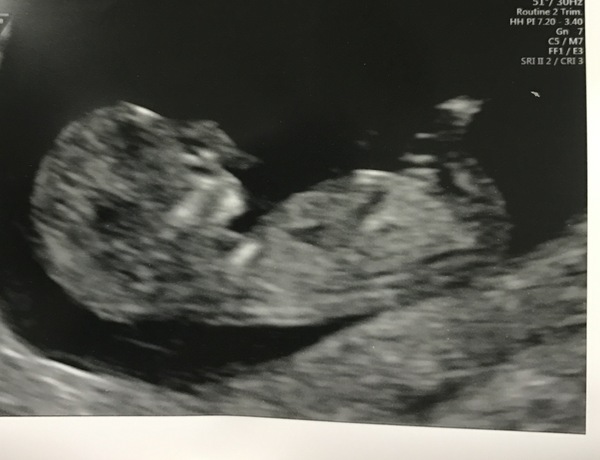

Just had my scan and it went so well. Baby measuring 12 weeks and wriggling around like mad. Ended up with 6 pictures because it was posing and making the sonographer laugh, well worth the £18 I did have to pay.